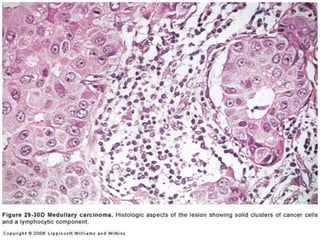

Medullary carcinoma

Soft, fleshy well defined mass mimics benign

6th decade

L.N metastasis common

Prognosis favourable

Highly Cellular

smears

Large pleomorphic

,undifferentiated

malignant cells with

irregular coarsely

granular nuclei with v

large nucleoli

Many lymphocytes

in background